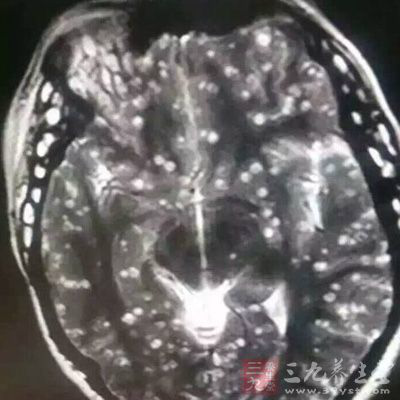

今年23岁的婷婷(化名)来自迪庆藏族自治州德钦县雨崩村。近,之前一直身体健康的她忽然出现了头疼、大腿疼的症状。紧接着,全身多处地方都出现不明原因的疼痛。严重时甚至连眼睛都会疼,还一直不停地流眼泪。这样的情况持续一个多月后,上周,婷婷辗转来到神经内科就诊。为了找出婷婷全身疼痛的原因,医生建议她先做脑部核磁共振和全身CT扫描检查。拿到检查结果后,就连行医多年的专家都惊呼:“简直太不可思议了。”——从各种影像检查资料来看,婷婷的大脑、眼球后方、大腿、腹壁、背部肌肉多个地方都长满了虫子,就连舌头、面部肌肉也有感染。抽血检查更进一步证实,婷婷的囊虫抗体是阳性,属于囊虫感染。

通过检查医生发现,婷婷的大脑里也有囊虫钙化现象。“这表示已有囊虫死去,说明囊虫感染的时间已经比较长。而且患者眼球突出,视网膜出血,全身多处感染,还伴有癫痫发作。”神经内科主任医师说,这么严重的囊虫感染,他也是第一次遇到。